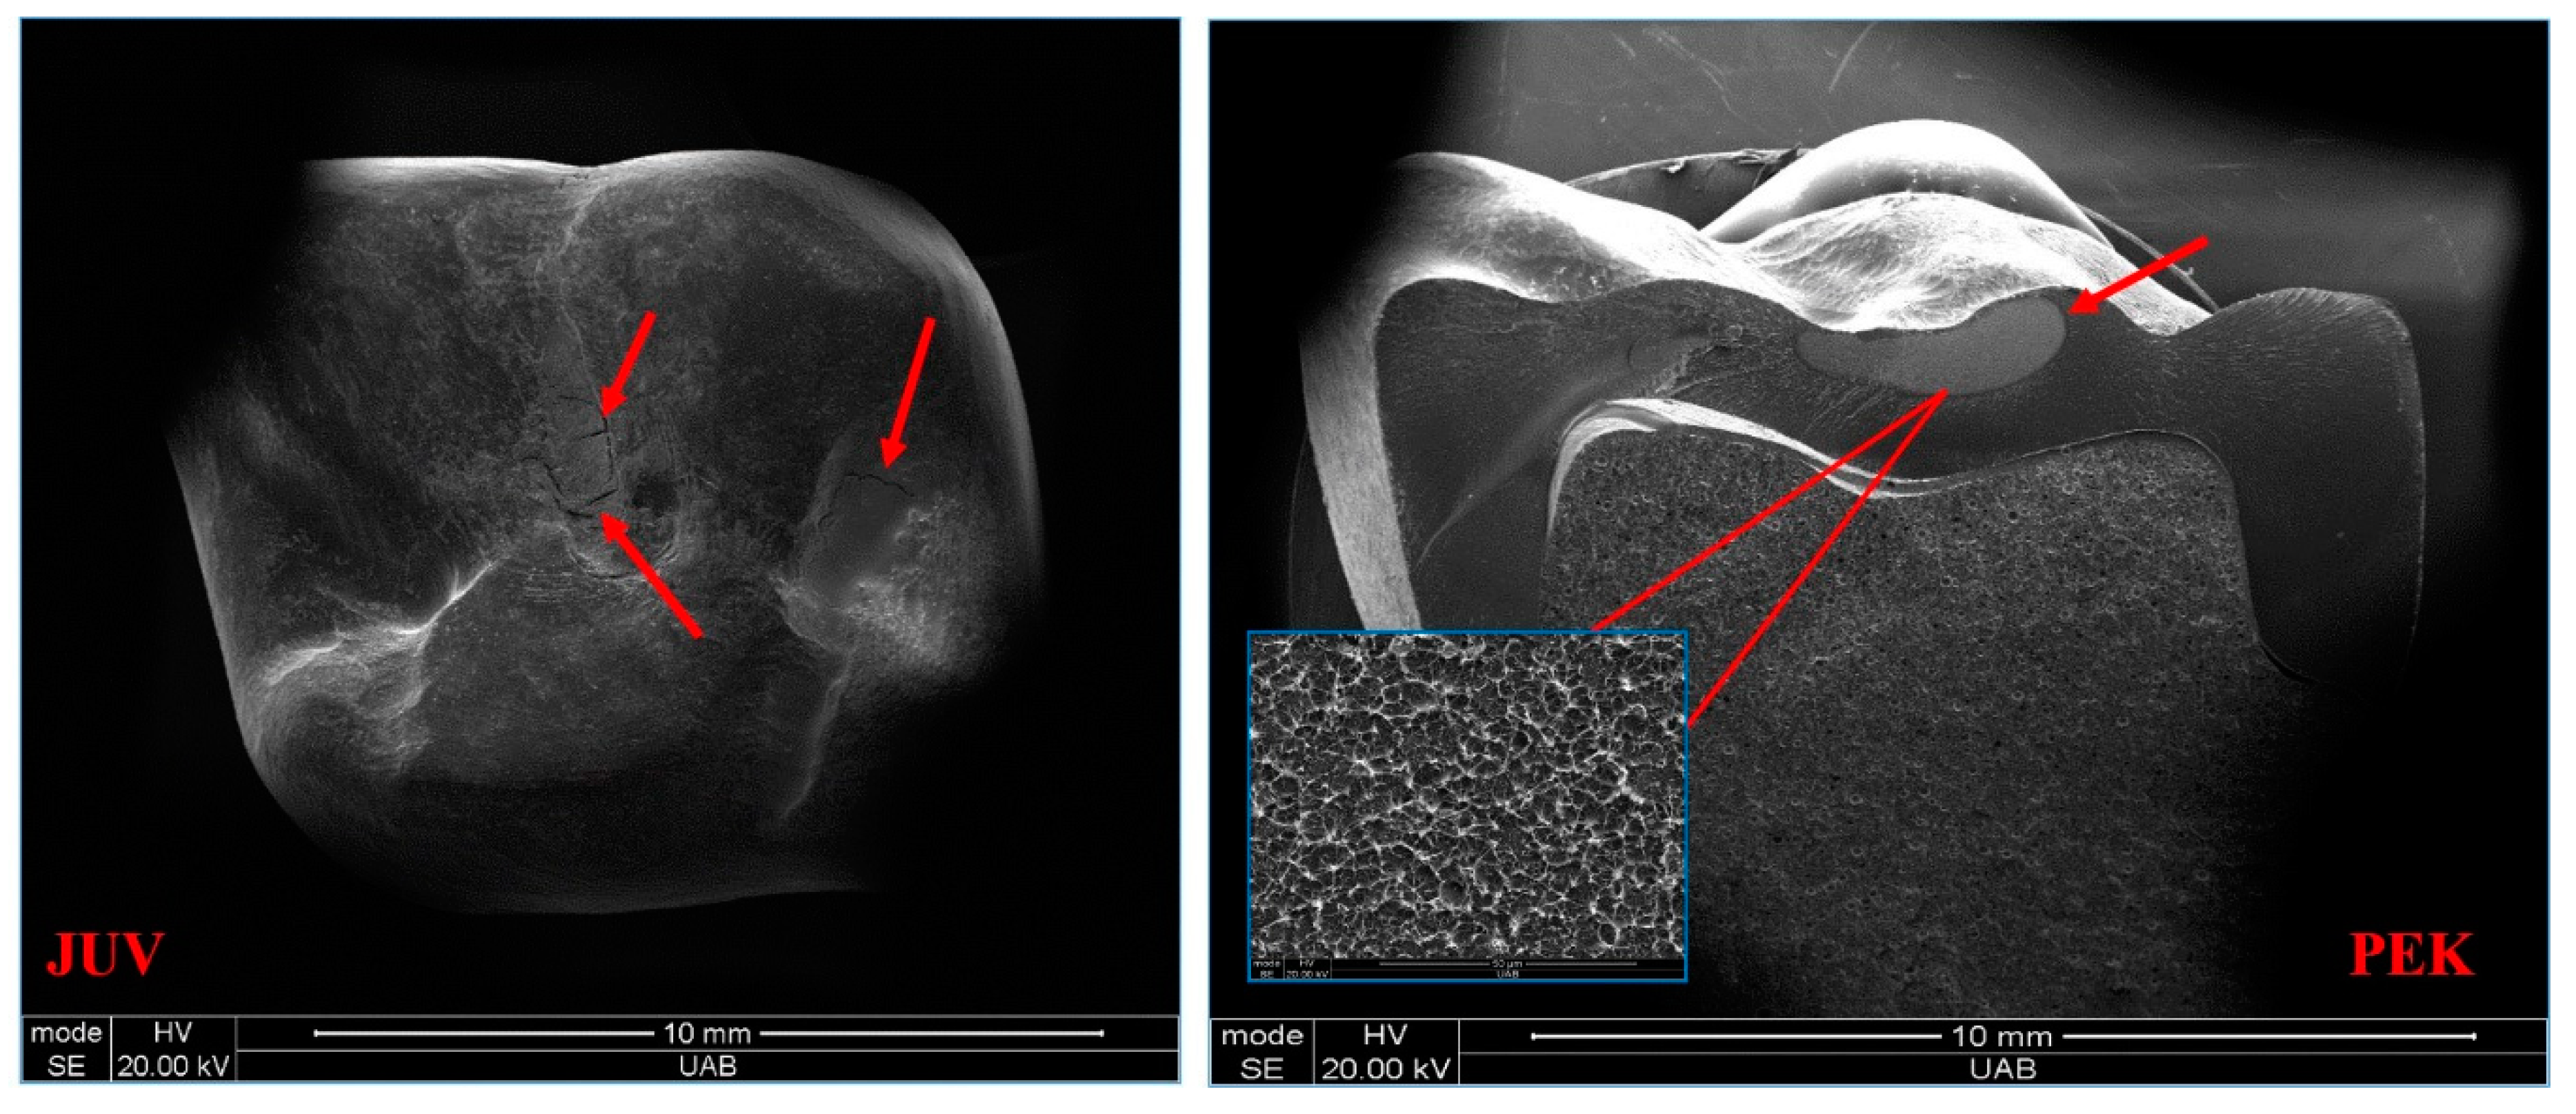

- The JUV specimens failed by deformation only, while the TRI specimens failed by deformation and cracks. The PEK specimens failed by fracture.